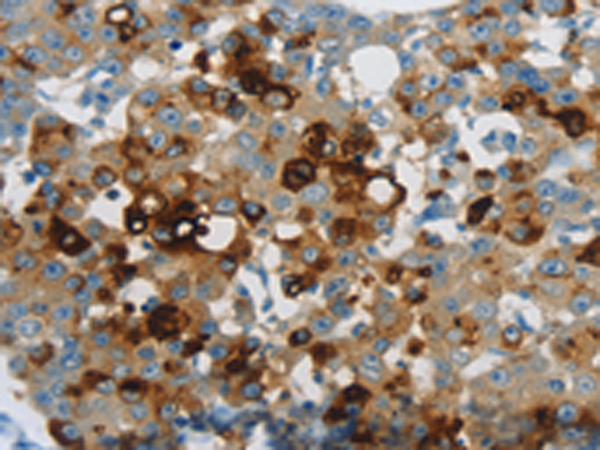

分类: 科研抗体货号: P11280别名: 24p3, MSFI, NGAL应用: WB,IHC反应种属: Human